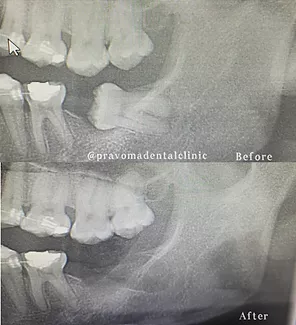

Cutting edge technology including, Endodontic machine, intra-oral digital X-ray machine and a Panoramic X-ray machine are available at Pravoma Dental Clinic to take routine Dental X-ray’s to make sure you have no cavities.

Root canal treatment (also called Endodontics) is needed when there is an infection in your pulp, through tooth decay or the tooth is damaged by an injury to your mouth. This infection may spread through the root canal system, which could eventually lead to a dental abscess, causing a great deal of discomfort or pain. If root canal treatment is not carried out, the tooth may need to be taken out. Our Dentist can perform root canal treatment to stop the infection from spreading and will preserve as much of your tooth as possible. Using specific techniques and advanced equipment, you will receive a local anaesthetic, and the treatment overall should feel no different to having an ordinary filling placed. The aim of the treatment is to remove all infection from the root canal. The root is then cleaned and filled to prevent any further infections. A temporary filling is put in on the first appointment, and the tooth is left to settle. The tooth is checked at a few days later, and when all the infection has cleared, the tooth is permanently filled. Root canal treatment is a skilled and time-consuming procedure, and most courses of treatment will involve two or more visits. To keep your mouth in shape, we recommend you come in for regular hygiene appointments and dental check-ups.